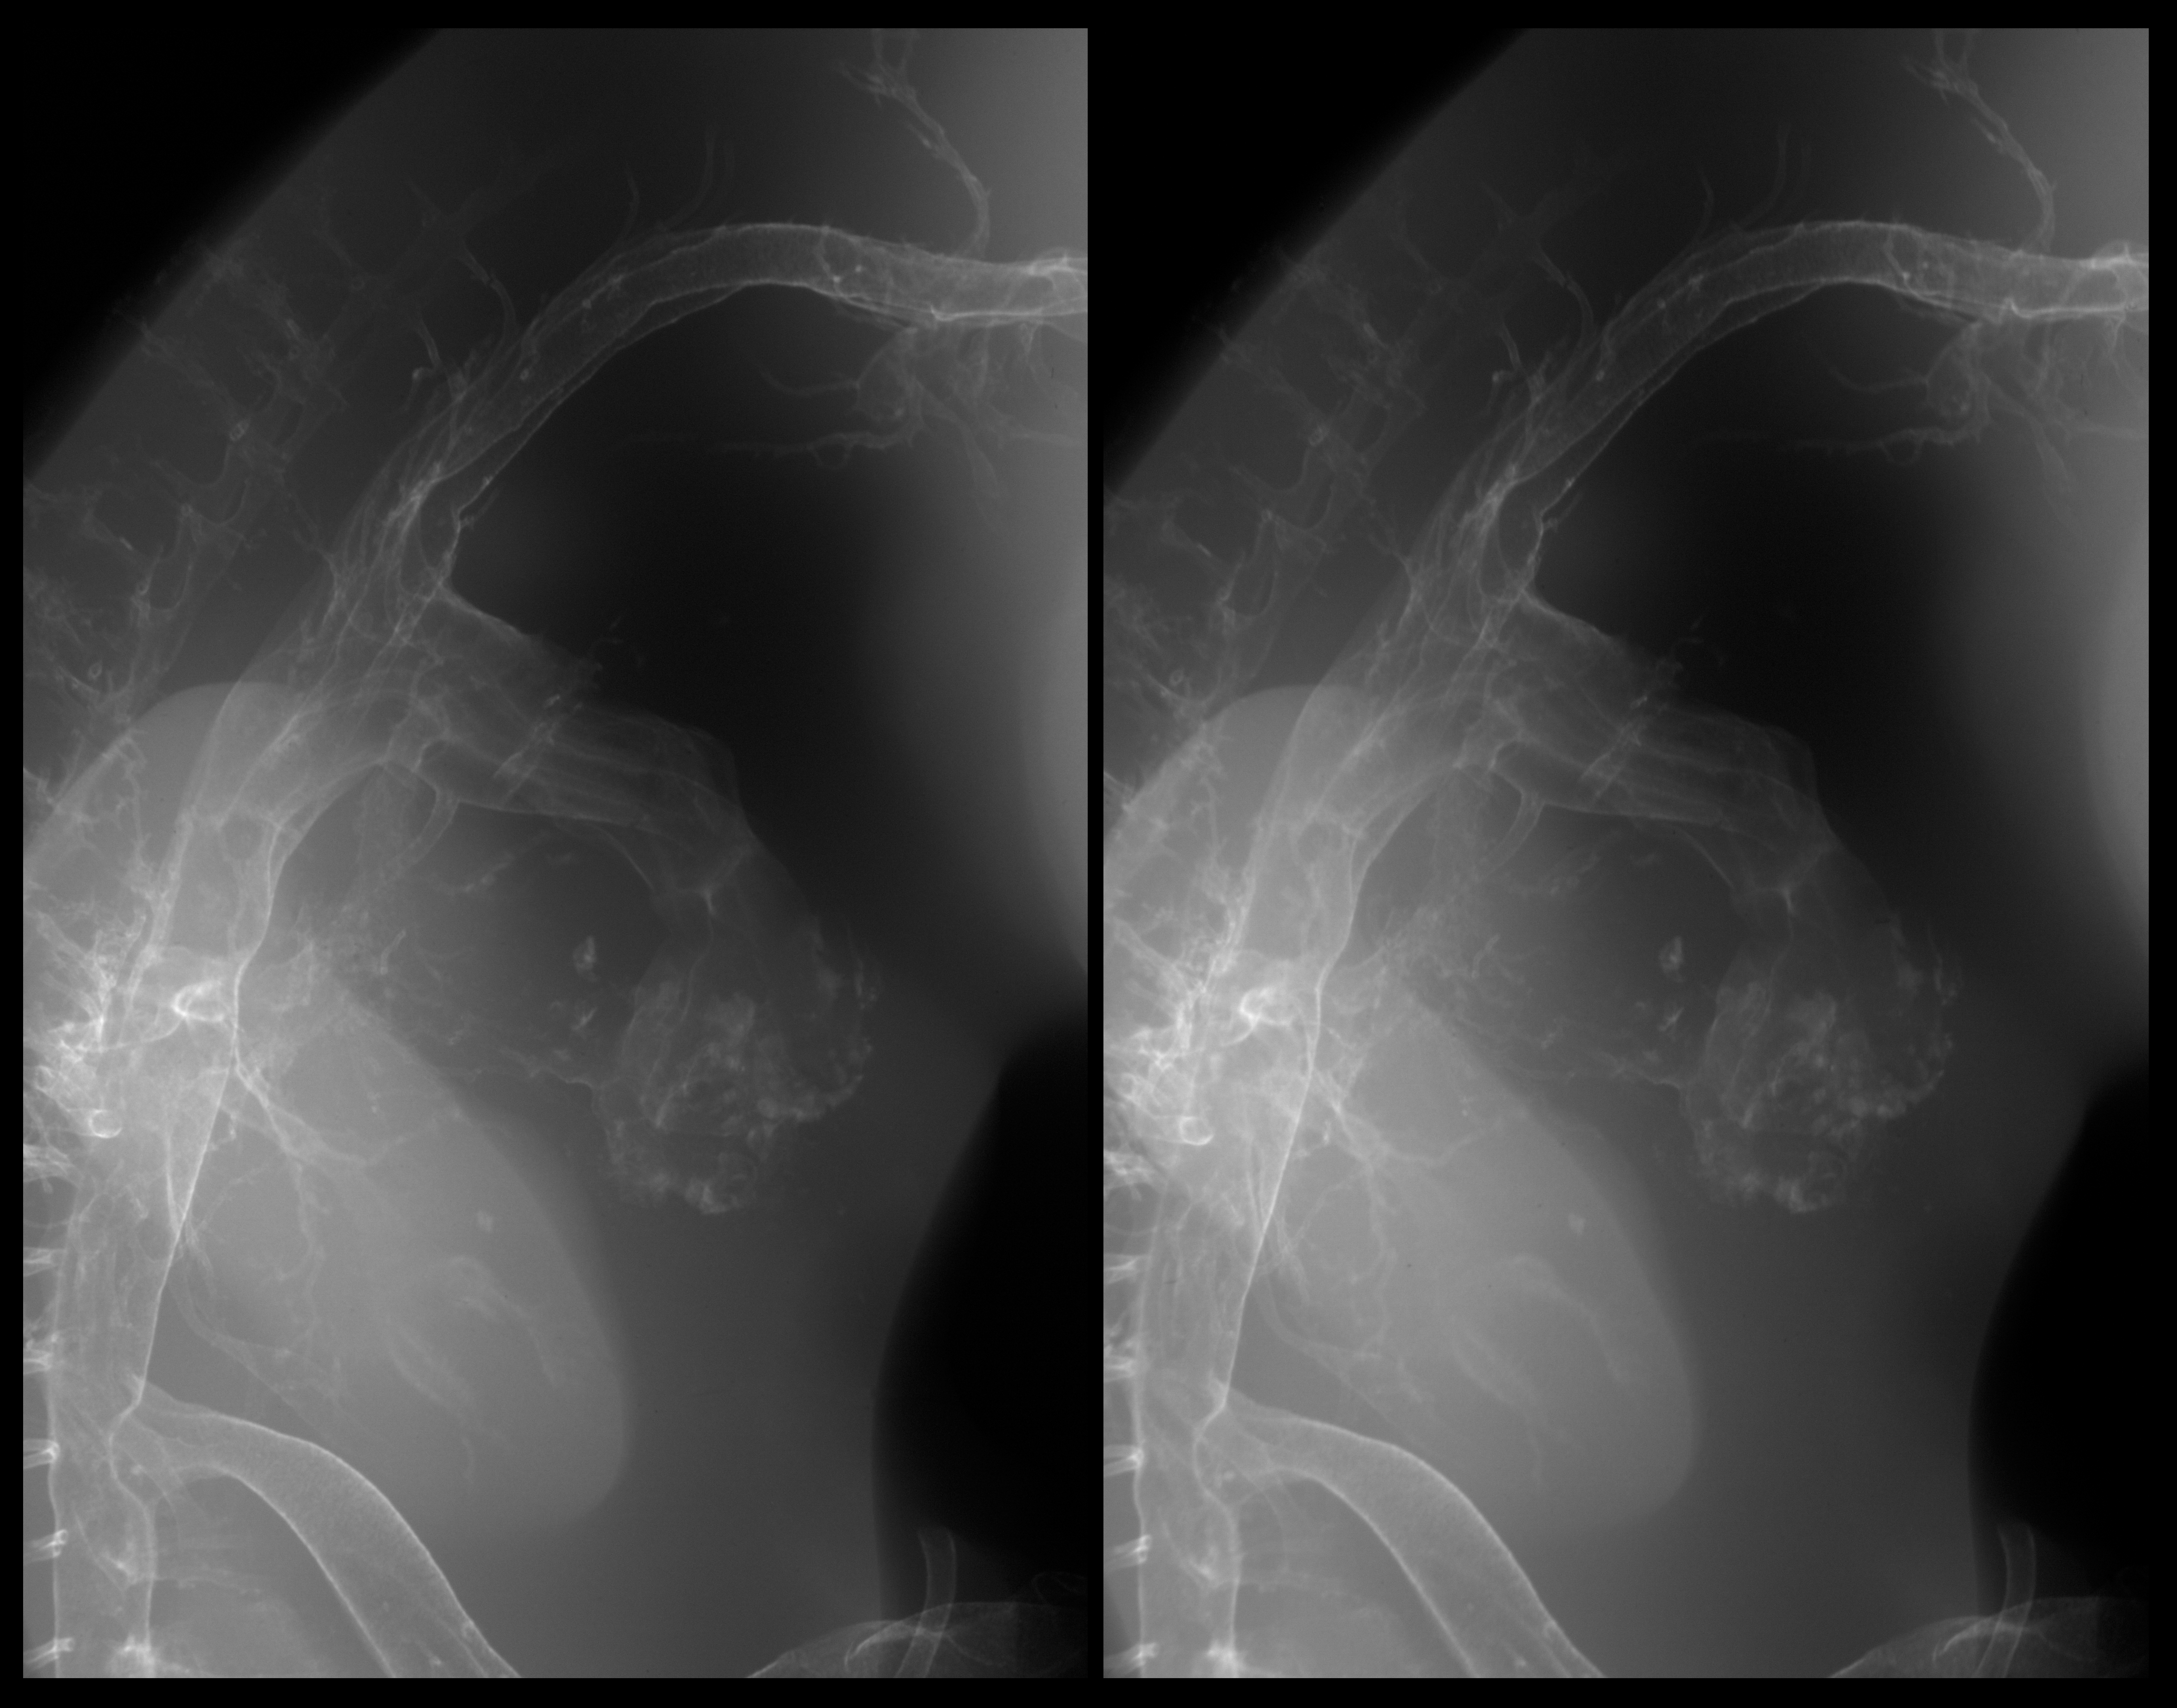

Stereo X-Ray Micrographs